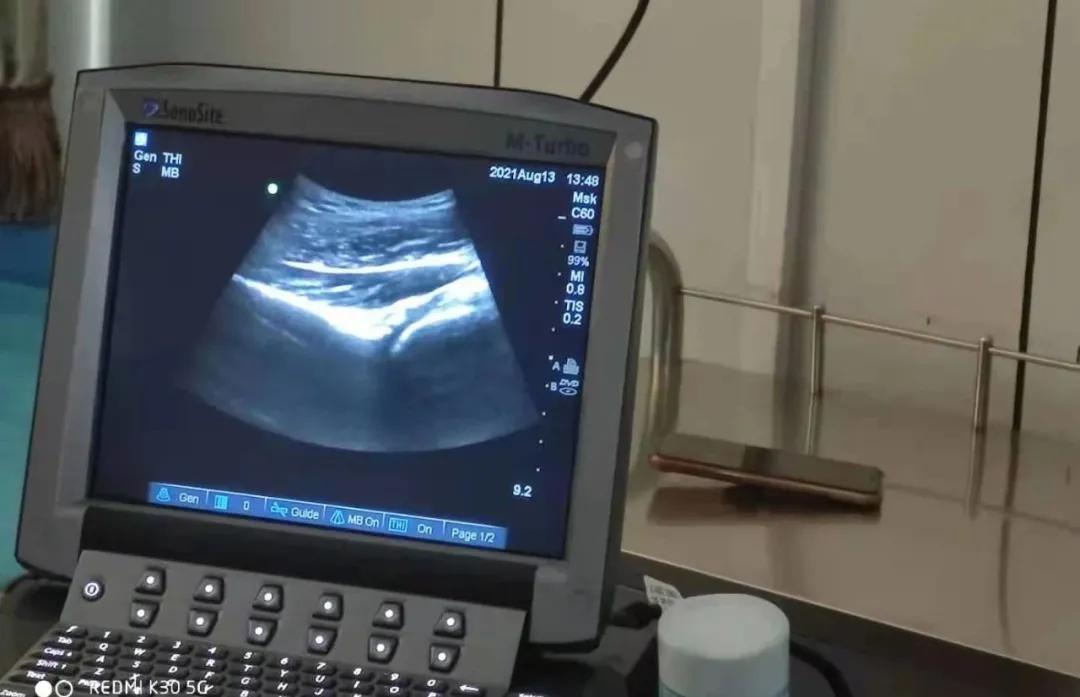

随着超声技术的进步,越来越多的临床医生运用超声技术解决临床问题,对于我们疼痛科医生来说, 可视化超声引导无疑是为我们以前凭经验、凭感觉穿刺送来了光明。

医师能够通过超声成像技术直接观察神经及周围的结构,在实时的超声引导下精确定位靶向治疗目标,同时,超声能够清晰的显示外周神经及其主要分支的走形及结构,这就使超声引导下的神经阻滞治疗能够做到高度特异性和选择性,实施 精准的神经阻滞,减少对周围组织的损伤。

还可通过超声观察局麻药的注射过程,从而保证局麻药均匀的扩散到神经周围,阻滞效果更加确切,同时也极大地减少了并发症的发生,成为了医生的“第三只眼睛”。如果说采用传统解剖定位方法神经阻滞是盲人在探路的话,而超声引导穿刺技术是真正赐予了这位盲人明亮的双眼。